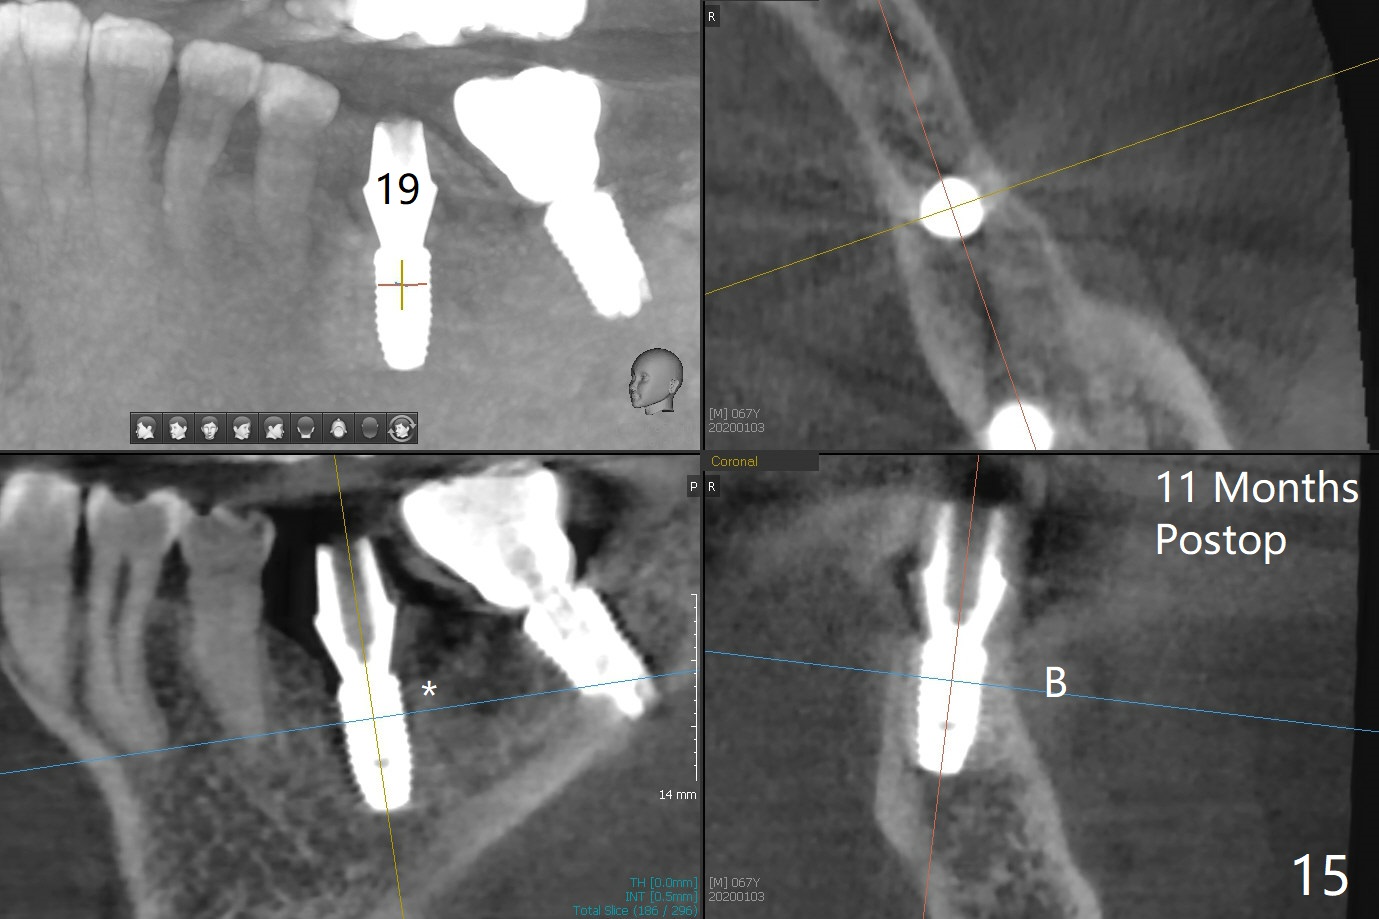

Probably due to severe infection at #19, pain control is difficult. Osteotomy has to be stopped 1.5 mm short of the design. PA taken with a 4.5x10 mm dummy implant does not show the Inferior Alveolar Canal (Fig.1), whereas CT does (Fig.2). With 6 mm clearance, block anesthesia is administered. A 5x10 mm definitive implant is placed with ease (Fig.3). The buccal bony defect is repaired by allograft (Fig.3,4 *), while the soft one by 3 pieces of PRF membrane (Fig.5). The latter is fixed in place by applying setting acrylic as an immediate provisional (Fig.6 P) over the wound, around the abutment (A) and locking into the undercut of the neighboring tooth/implant crown. The patient feels great postop. The gingiva is healthy around the provisional 8 days postop (Fig.7). The patient remains asymptomatic with the healthier gingiva surrounding the simplified provisional 22 days postop, as compared to 8 days postop (Fig.8). The socket heals when the simplified provisional is removed 1.5 months postop (Fig.9-12). The bone graft (Fig.11 ^) seems to have become a part of the regenerated gingiva. The abutment has been dislodged for 2 week (Fig.14 (3 months postop). The bone graft, albeit decreased, is 2 mm subgingival (red dashed line). There is bone distal to the implant 11 months postop (Fig.15 *). There is no bone loss 2 years postop; the UF abutment is completely seated (Fig.16).